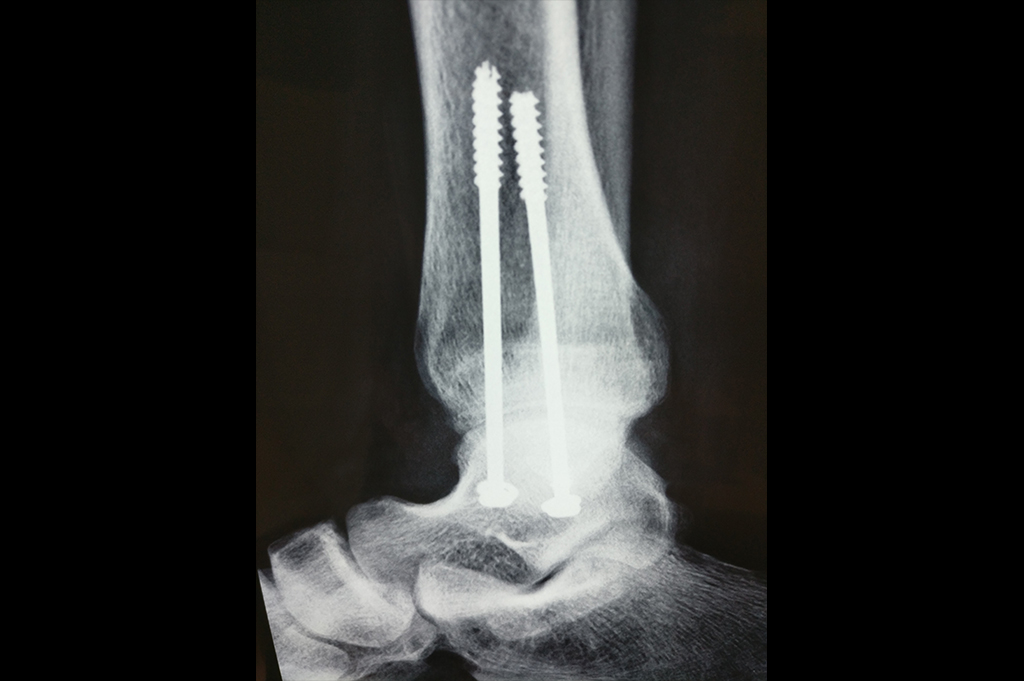

Calcaneum

Scaphoid